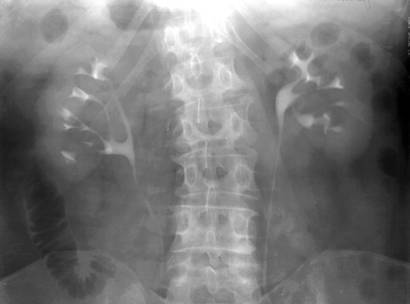

Fig. 69 – Rinichi polichistici (alungire, ingustare si dezorientare a calicelor bilateral)

2. RINICHIUL POLICHISTIC

Este o afectiune bilaterala, mai frecventa la femei. Parenchimul renal din zona polilor si a capsulei contine formatiuni chistice multiple de dimensiuni variabile, pline cu lichid sub tensiune. Se insoteste de degenerescenta chistica si in alte organe. Pielografia ascendenta si ureteropielografia retrograda dau datele cele mai evidente: - boselarea contururilor umbrei renale; - marirea umbrei renale, ce depaseste marginea interioara a psoasului; - simetrie bilaterala; - alungirea bazinetului si a calicelor (aspect de paianjen); dilatarea extremitatilor papilare ale calicelor; - dezorientarea tijelor caliceale ce pornesc dintr-un bazinet normal; - amputatii caliceale; - opacitati izolate, mari, ce sunt expresia comunicarii chistelor cu calea de excretie; - imagini cavitare ce apar prin supurarea chistelor in calea de excretie. Bazinetul este usor ingustat iar ureterul impins spre coloana vertebrala. Angiografia evidentiaza modificarea directiei ramurilor arterelor.